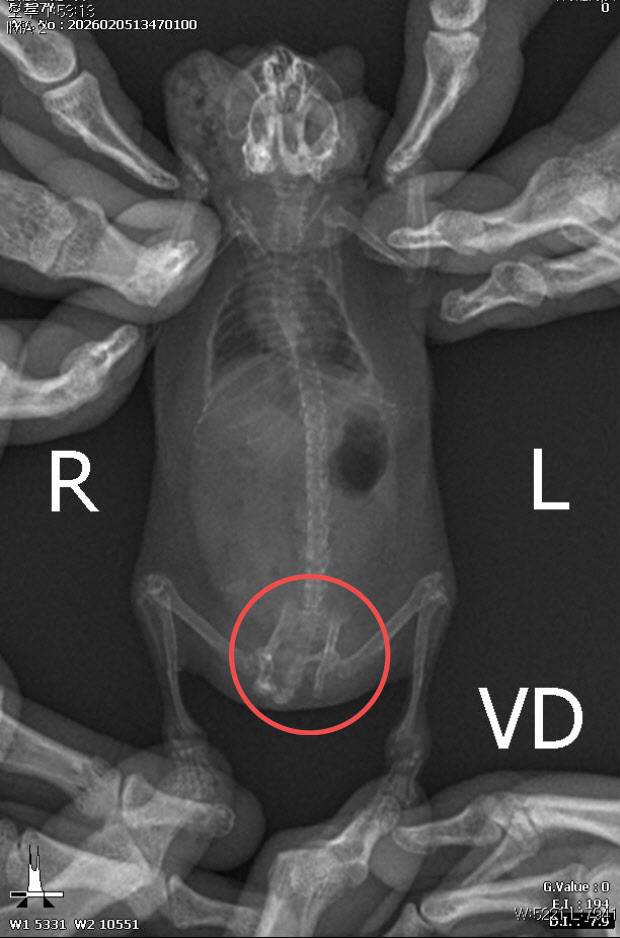

검진결과 재골절·영양부족 등 상태심각

이어 “귀가 찢어지는 등 다수의 개체에서 교상 흔적이 관찰됐으며 일부 개체는 장기간 반복된 타박상으로 인해 골절 및 재골절이 의심되는 정황까지 확인됐다”고 덧붙였다.